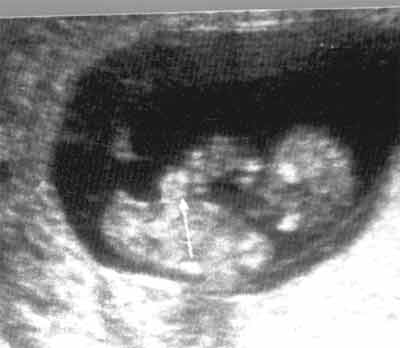

Coupe Longitudinale